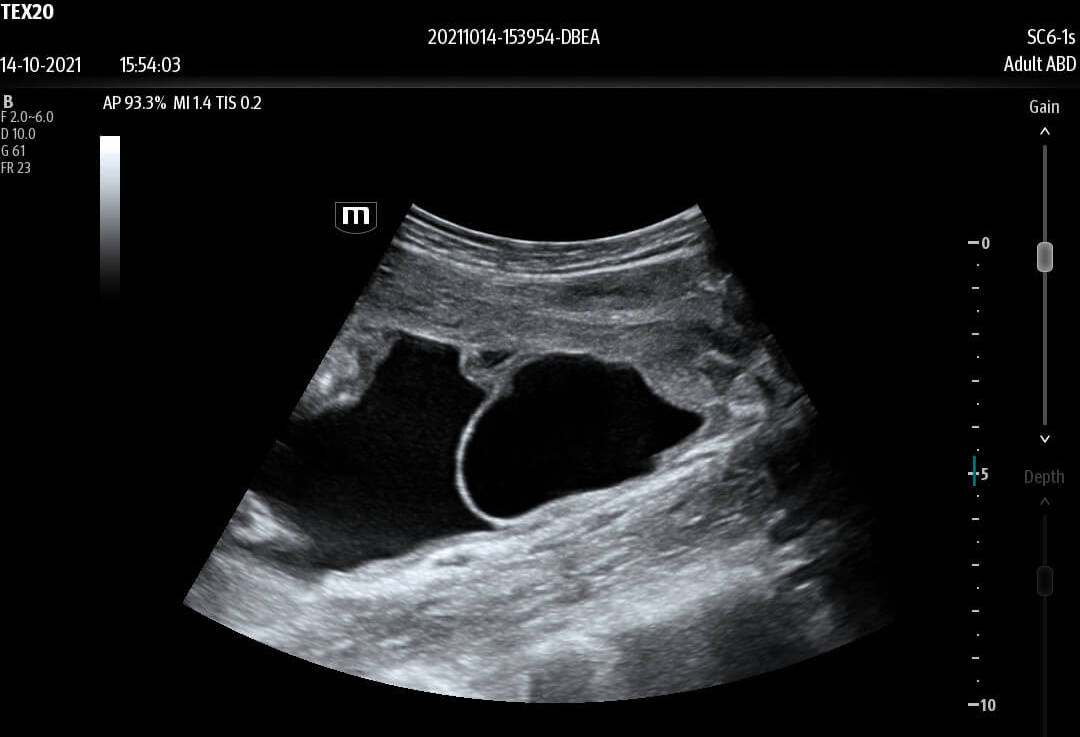

Enhancing Clinical Confidence

Advanced Technologies